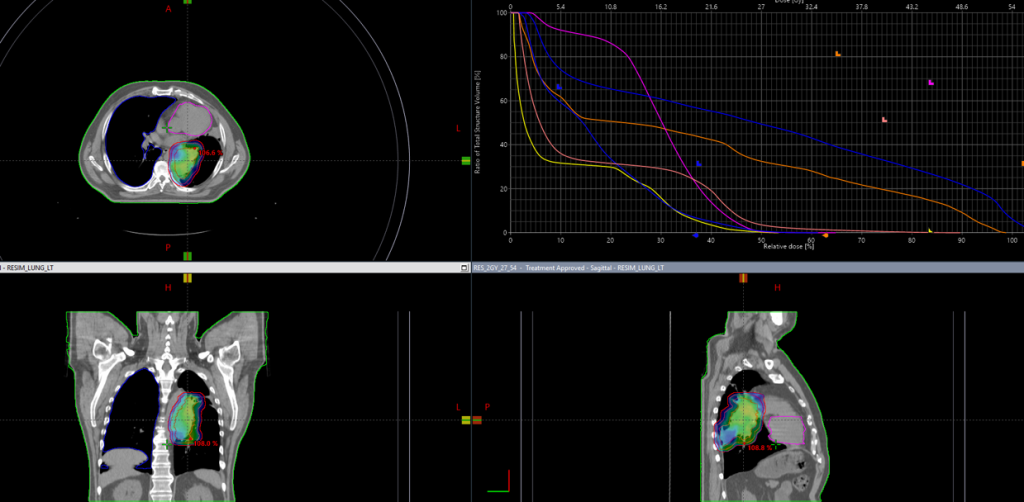

Выполнено оконтуривание на КТ срезах объемов мишени (GTV,CTV,PTV) и всех органов риска

22.07.2022г. выполнена повторная

КТ- топометрия органов грудной клетки

С 25.07.2022 начат курс лучевой терапии

На аппарате HALCYON с ежедневной KV-визуализацией

Одновременная химиотерапия по схеме паклитаксел+карбоплатин еженедельно

В Институте ядерной медицины мы регулярно используем ежедневную KV-визуализацию (компьютерная томография с коническим пучком) для более точной локализации опухоли и проведения прецизионной, то есть суперточной лучевой терапии. Особенно важна ежедневная визуализация при раке легкого, когда объем облучения может значительно и быстро изменяться, в результате резорбции опухоли или вследствие осложнений, например ателектаза. Так же ежедневная визуализация позволяет уменьшить отступ на погрешность в укладке пациента, тем самым снижает лучевую нагрузку на критические органы